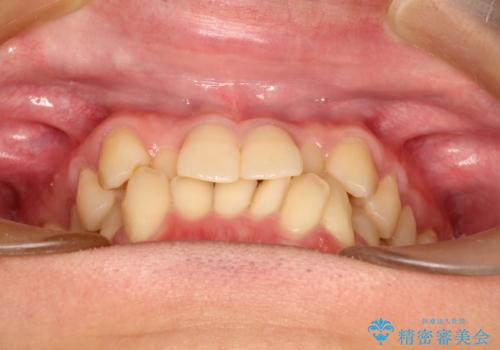

- 前歯のがたつきが気になるとのことで来院されました。

骨格的なところと、上下の歯の大きさのことを考慮して、下の前歯を1本抜歯し、インビザラインにて矯正治療することとなりました。

上の前から2番目の歯がもともと小さかったため、最後にかぶせ物を装着することで、自然な仕上がりにできました。